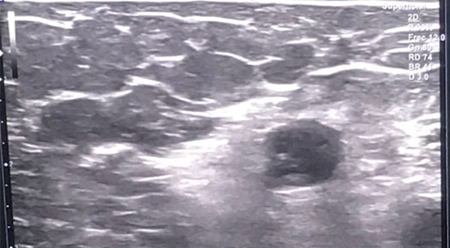

Previo a la técnica, se procede primero a la realización de un bloqueo axilar ecoguiado del miembro superior izquierdo con lidocaína 2 %. Posteriormente y tras comprobar la eficacia del bloqueo, se realiza la infiltración en el cuerpo de los neuromas. Dicha infiltración se realiza de forma ecoguiada, bajo visión directa en plano. Para ello se ubica la sonda lineal de alta frecuencia sobre las prominencias óseas inicialmente dolorosas de la paciente hasta identificar los cuerpos de los neuromas, visibles como estructuras redondeadas hipoecogénicas bien definidas. Tras su identificación, se introduce la aguja en plano hasta contactar con el cuerpo del neuroma, infiltrando en su interior un volumen de 3 ml de fenol 6 % acuoso. Este procedimiento se repite en cada uno de los neuromas previamente identificados, y posteriormente se cita a la paciente para control en consulta al mes.

Fig. 3. Visión ecográfica durante el procedimiento de uno de los neuromas tratados mediante neurólisis